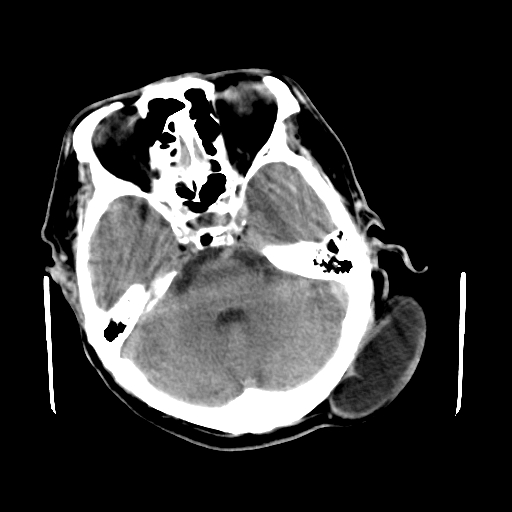

男,62岁,右侧肢体活动障碍不灵活三天,左侧头皮肿物十余年(ct值8hu)。

1)多发性腔隙性脑梗塞。2)脑白质病。3)脑萎缩。4)左侧枕顶部头皮下皮样囊肿,不排除脂肪瘤。

1)多发性腔隙性脑梗塞。2)脑白质病。3)脑萎缩。4)左侧枕顶部头皮下皮样囊肿或表皮样囊肿。